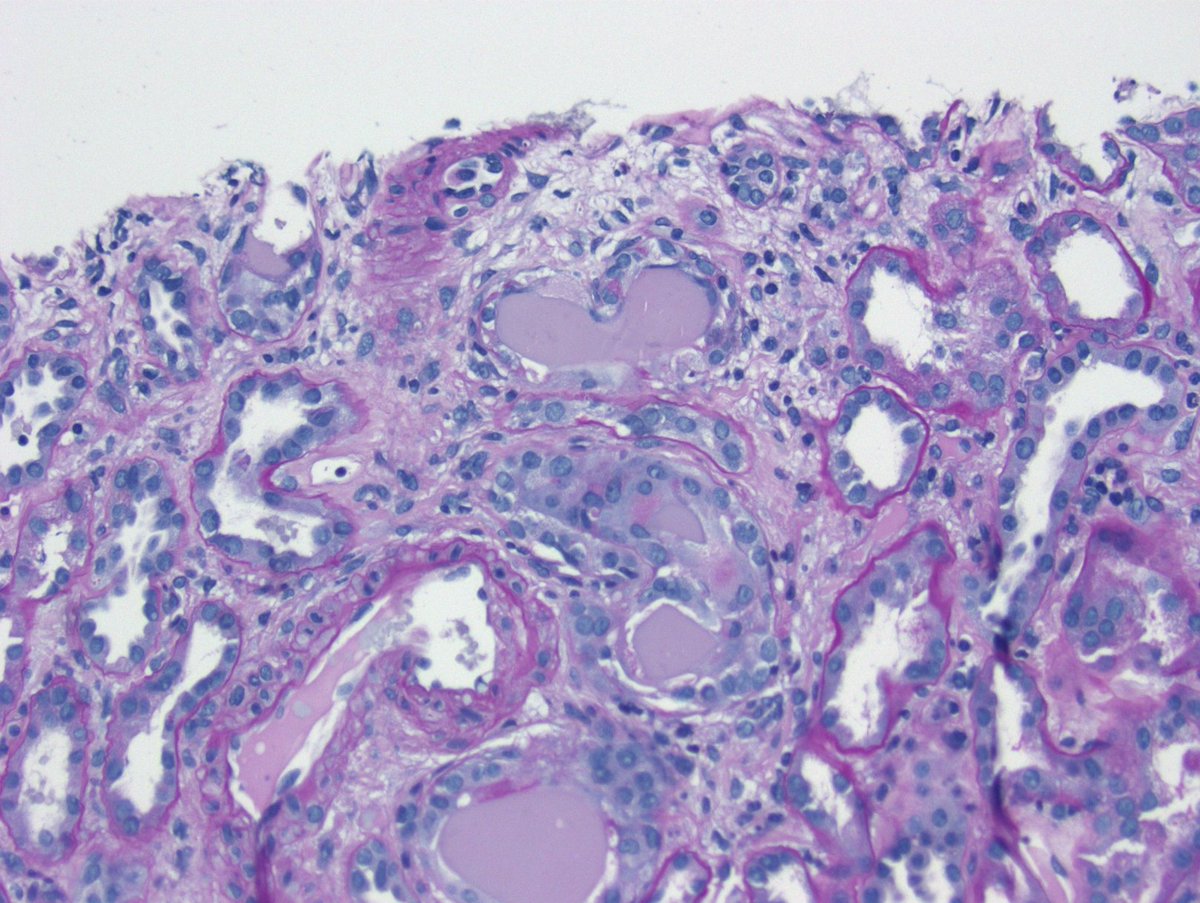

Long weekend often brings urgent cases. Here is one that was STATed, ended up showing anti-GBM GN. Diffuse crescents (nearly 100%). Linear IgG. #RenalPath